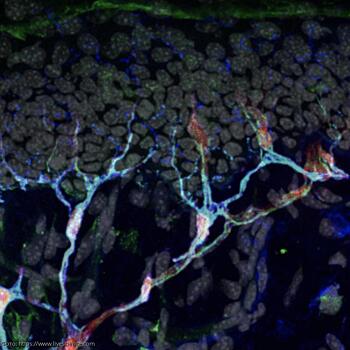

Исследователи обнаружили новый орган, расположенный под наружным слоем кожи. Орган состоит из нервов и сенсорных глиальных клеток, и именно он позволяет человеку почувствовать боль от укола. Согласно имеющейся в распоряжении ИА «Экспресс-Новости» информации, ранее считалось, что люди ощущают боль от укола через нервные окончания, которые располагаются прямо под наружным слоем кожи. Теперь же новое исследование предполагает, что не только этот факт, но нервы, запутанные в специальных клетках, заставляют нас вздрогнуть. «Мы давно знаем, что в коже существуют различные виды сенсорных органов, но те, о которых мы знали, были связаны только с ощущением прикосновения, – рассказал старший автор исследования Патрик Эрнфорс, профессор биологии тканей в Каролинском институте в Швеции. – Эта сеть разветвленных клеток и нервов является новым «сенсорным органом», потому что она реагирует на внешние сигналы и передает эту информацию в мозг. В отличие от других известных сенсорных органов под кожей, этот играет роль в восприятии боли». По сути, здесь речь идет о том, что данный орган чувствителен к уколам или ударам, и, будучи активирован давлением, он посылает сигналы в мозг. Затем мозг посылает сигналы на место укола, который говорит нам чувствовать боль. По словам Эрнфорса, клетки, из которых состоит этот орган, называемые клетками Шванна, кажутся «немного похожими на осьминога» с длинными выпуклыми щупальцами, выступающими в окружающие нервы. Как известно, клетки Шванна окружают и изолируют нервы. Но чтобы выяснить функцию этих специфических клеток Шванна в коже, исследователи проверили, что произошло, когда они были выключены у мышей; для этого ученые использовали метод под названием «оптогенетика». Они вставили в геномы светопоглощающий белок, и этот белок включил клетки Шванна, когда было поглощено достаточно света. Когда клетки были активированы, мыши демонстрировали поведение, указывающее на то, что они чувствовали боль. Мыши также демонстрировали поведение, связанное с копингом, такое как облизывание и встряхивание лап. По словам Эрнфорса, «как будто вы обжигаете себя, а затем промываете руку под холодной водой», мыши пытались облегчить боль. «Когда мы выключаем эти клетки, животные испытывают гораздо меньшее давление и боль» в ответ на болезненные ощущения покалывания, чем у типичных мышей. Однако когда исследователи выключили эти клетки и затем проверили животных на чувствительность к холоду и жаре, мыши могли чувствовать эти ощущения так же хорошо, как когда клетки не выключались. Это означает, что сами нервы «вероятно, гораздо важнее, чем терминальные клетки Шванна, для ощущения тепла и холода», в то время как клетки Шванна более важны для ощущений давления, - отметил Эрнфорс. Под микроскопом эти клетки Шванна быстро активируются и посылают сигналы другим нервам, когда их тыкают. Теперь Эрнфорс хочет выяснить, имеют ли эти клетки какое-либо отношение к хронической боли: «Хроническая боль стала центром внимания, поскольку опиоидная зависимость продолжает истощать жизни и приводить к смертности», – пишет в комментарии, сопровождающем исследование, аспирант Райан Доан и старший научный сотрудник Келли Монк из Института Фоллума в Орегоне. – Подобные осьминогу клетки Шванна являются «новой потенциальной клеткой-мишенью для обезболивающего лечения».